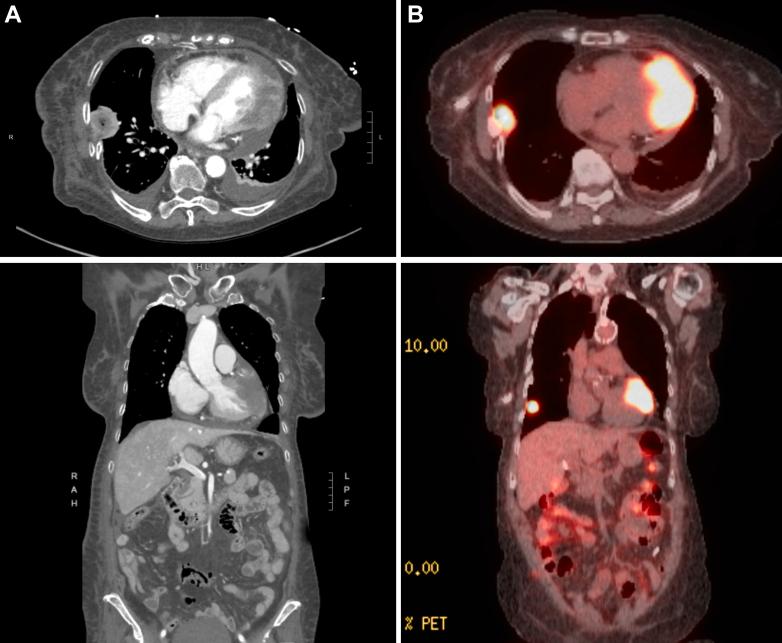

酷似侧壁ST段抬高型心肌梗死的肺梭形细胞癌心脏转移

Cardiac Metastasis of Pulmonary Spindle Cell Carcinoma Mimicking Lateral ST-Segment Elevation Myocardial Infarction.

Cardiac metastasis of malignant tumors is rare but can mimic myocardial infarction (MI). We review a case of myopericardial metastasis presenting as ST-segment elevation MI (STEMI) and the clinical characteristics of cardiac injury from malignant metastasis.

CASE SUMMARY

A 78-year-old woman with a history of breast cancer and recently diagnosed pulmonary spindle cell carcinoma presented with progressive tongue pain related to metastasis. Her electrocardiogram showed ST-segment elevations in leads I, aVL, and V with reciprocal changes in leads III and aVF on a background of atrial fibrillation. She had no chest pain, but elevated lactate (6.6 mmol/L) and high-sensitivity troponin T (45 ng/L) raised concern for STEMI. Coronary angiography revealed no obstructive coronary disease. Echocardiogram found an intramyocardial mass extending into the pericardium. The patient was transitioned to comfort care because of her poor oncologic prognosis.

TAKE-HOME MESSAGES: In advanced cancer, myocardial metastasis should be considered a cause of persistent ST-segment elevations. Echocardiography should be prioritized to identify structural abnormalities, such as malignant myocardial infiltration, whereas coronary angiography remains essential to rule out acute MI when clinically indicated.

恶性肿瘤的心脏转移罕见,但可酷似心肌梗死(MI)。我们回顾一例表现为ST段抬高型心肌梗死(STEMI)的心肌心包转移病例以及恶性转移所致心脏损伤的临床特征。

病例摘要

一名78岁女性,有乳腺癌病史,近期诊断为肺梭形细胞癌,因转移出现进行性舌痛。其心电图显示I、aVL及V导联ST段抬高,III及aVF导联有对应性改变,背景为心房颤动。她无胸痛,但乳酸水平升高(6.6 mmol/L)及高敏肌钙蛋白T升高(45 ng/L)引起对STEMI的关注。冠状动脉造影显示无阻塞性冠状动脉疾病。超声心动图发现心肌内有一肿块延伸至心包。由于其肿瘤预后差,患者转为姑息治疗。

要点

在晚期癌症中,应考虑心肌转移是持续性ST段抬高的原因之一。应优先进行超声心动图检查以识别结构异常,如恶性心肌浸润,而冠状动脉造影在临床有指征时对于排除急性心肌梗死仍至关重要。